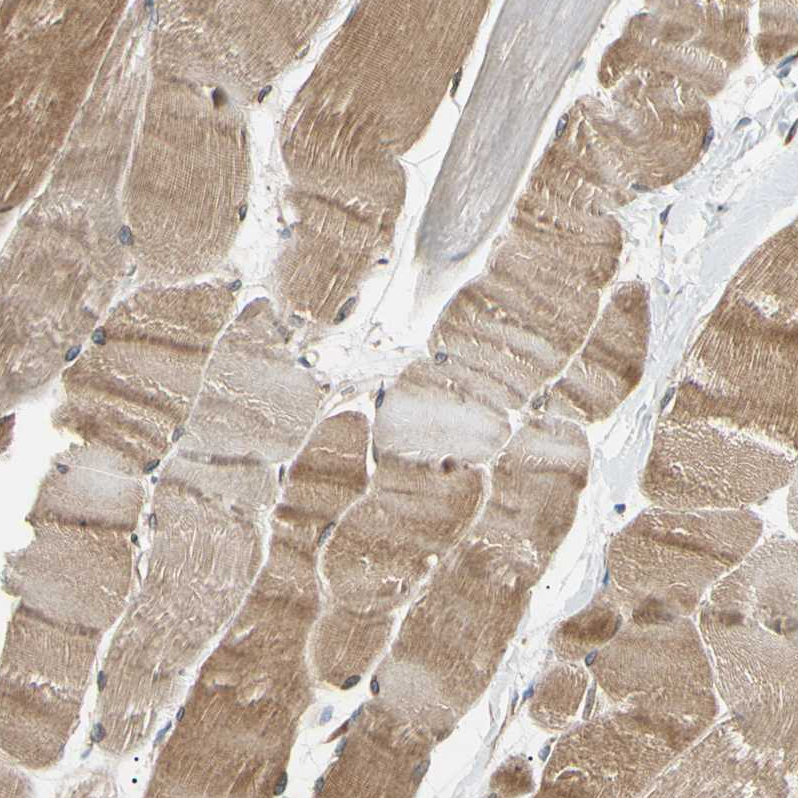

Immunohistochemical staining of human skeletal muscle shows moderate cytoplasmic positivity in myocytes.